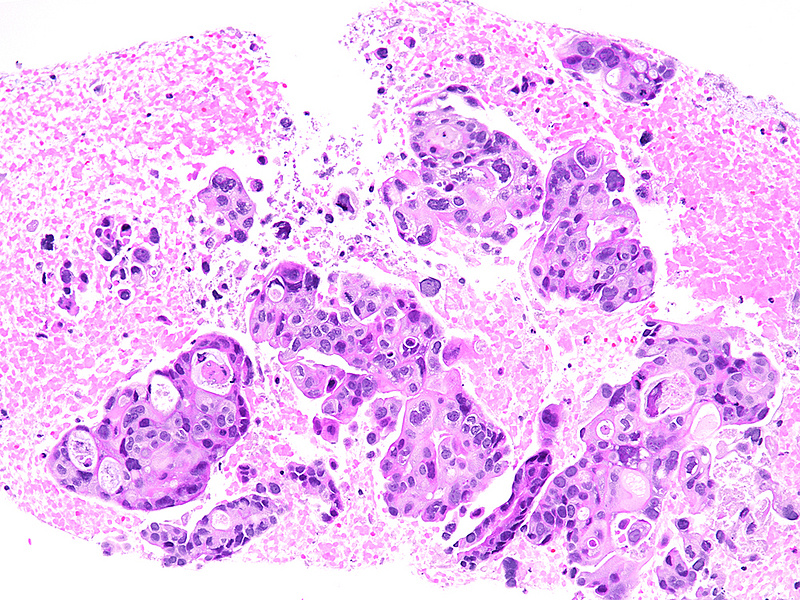

The well-sampled biopsy showed fragments of a necrotising carcinoma, arranged in isolated cells, small aggregates of cells and poorly formed glandular structures (Panels A-B). The tumour cells demonstrated abundant eosinophilic cytoplasm and severely pleomorphic, hyperchromatic nuclei with distinct nucleoli. Brisk mitotic activity was noted (Panel C). Within some clusters, the neoplastic cells had a more polygonal appearance, with intercellular desmosomes, more basophilic cytoplasm and evidence of dyskeratosis (Panels D-E).

By immunohistochemistry, the tumour cells were strongly and diffusely positive for CK7 (Panel F), focally positive also for p40 (Panel G) and CK20 (not shown). Ki67 labelling index confirmed the suspected high proliferation rate, estimated between 40-50% (Panel H). The immunohistochemical screening for DNA mismatch repair (MMR) deficiency showed no loss of protein expression. A final diagnosis of poorly (to undifferentiated) adenocarcinoma of the pancreas with squamous differentiation (consistent with adenosquamous carcinoma) was made.